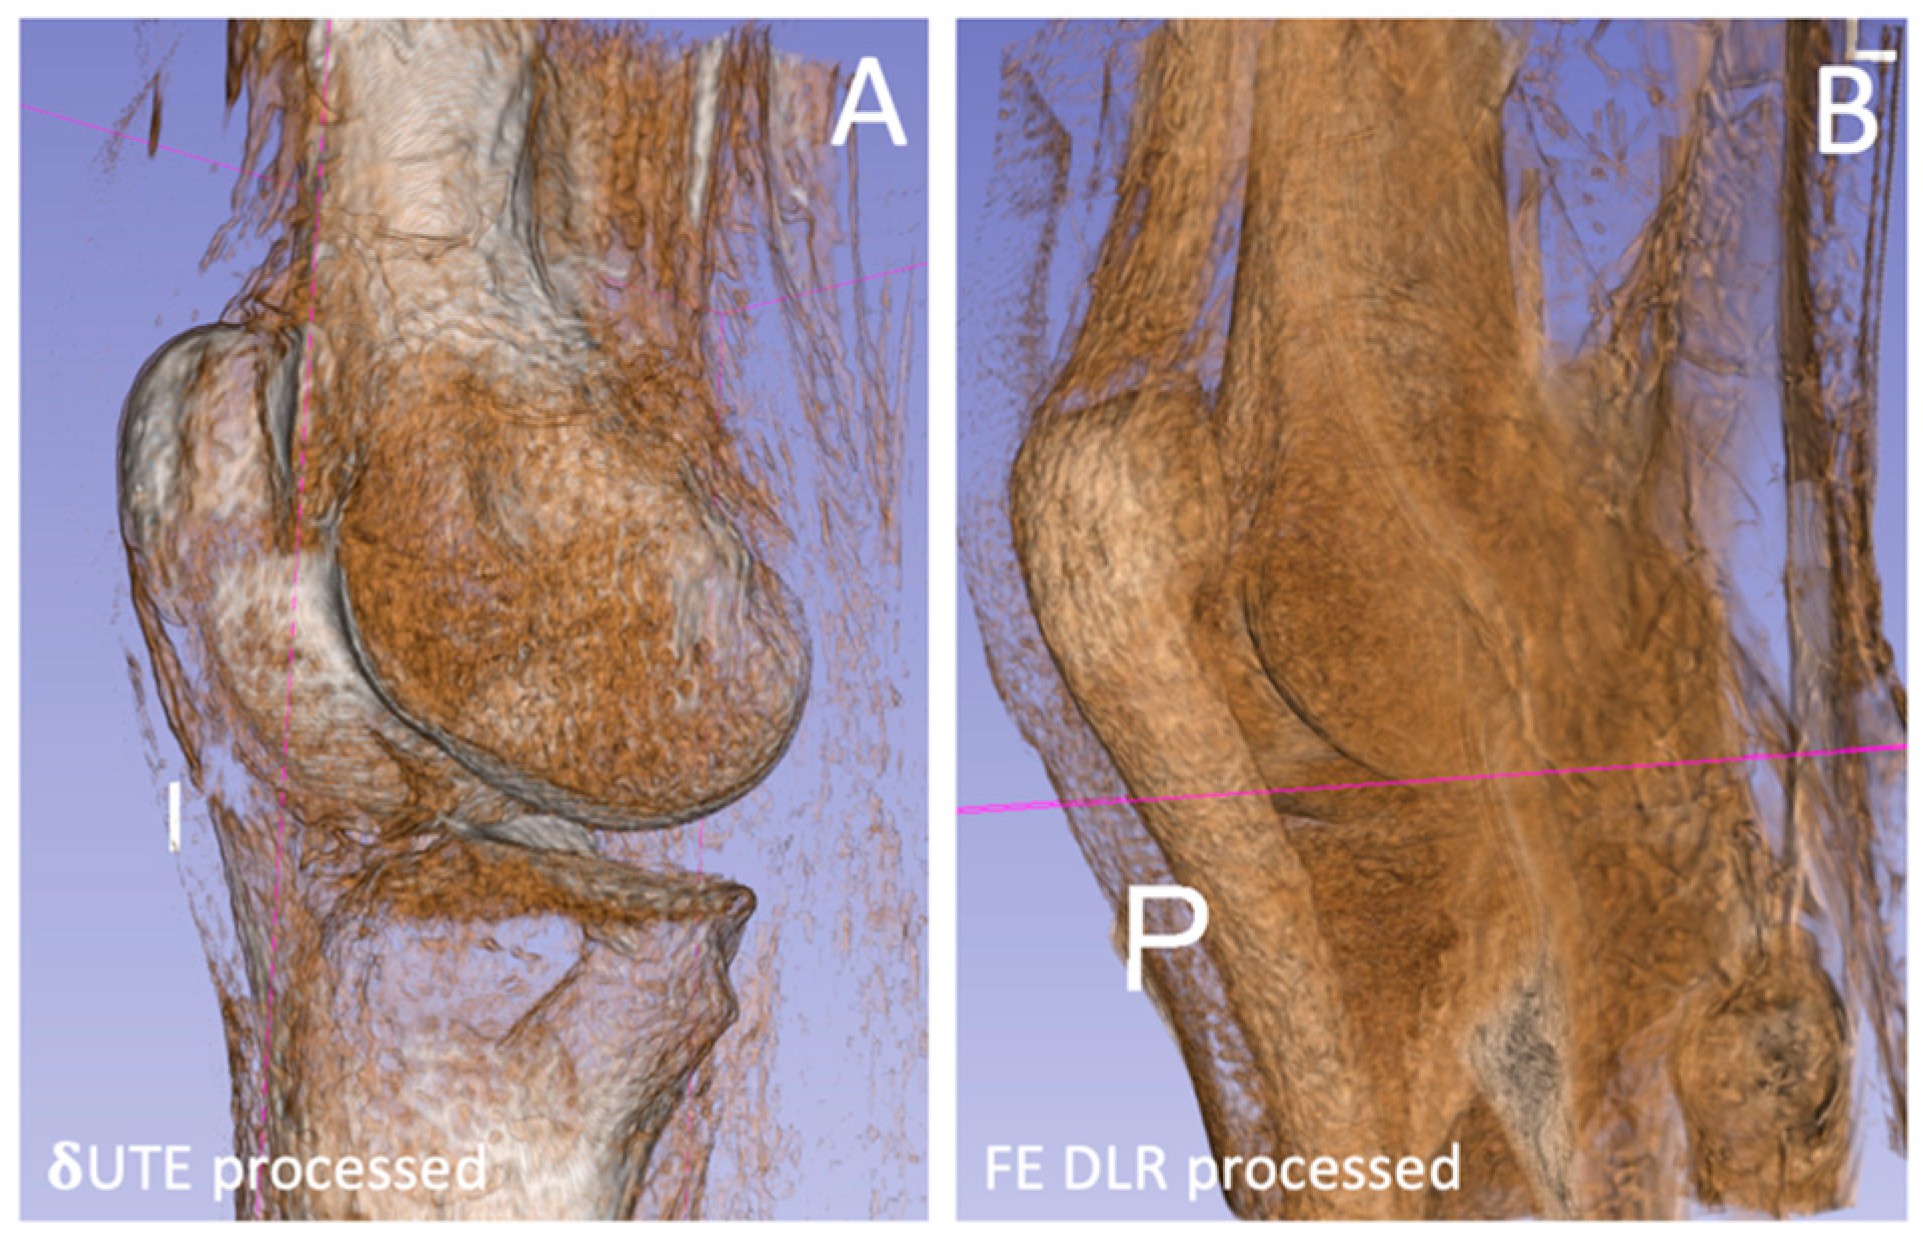

Bone Imaging of the Knee Using Short-Interval Delta Ultrashort Echo Time and Field Echo Imaging